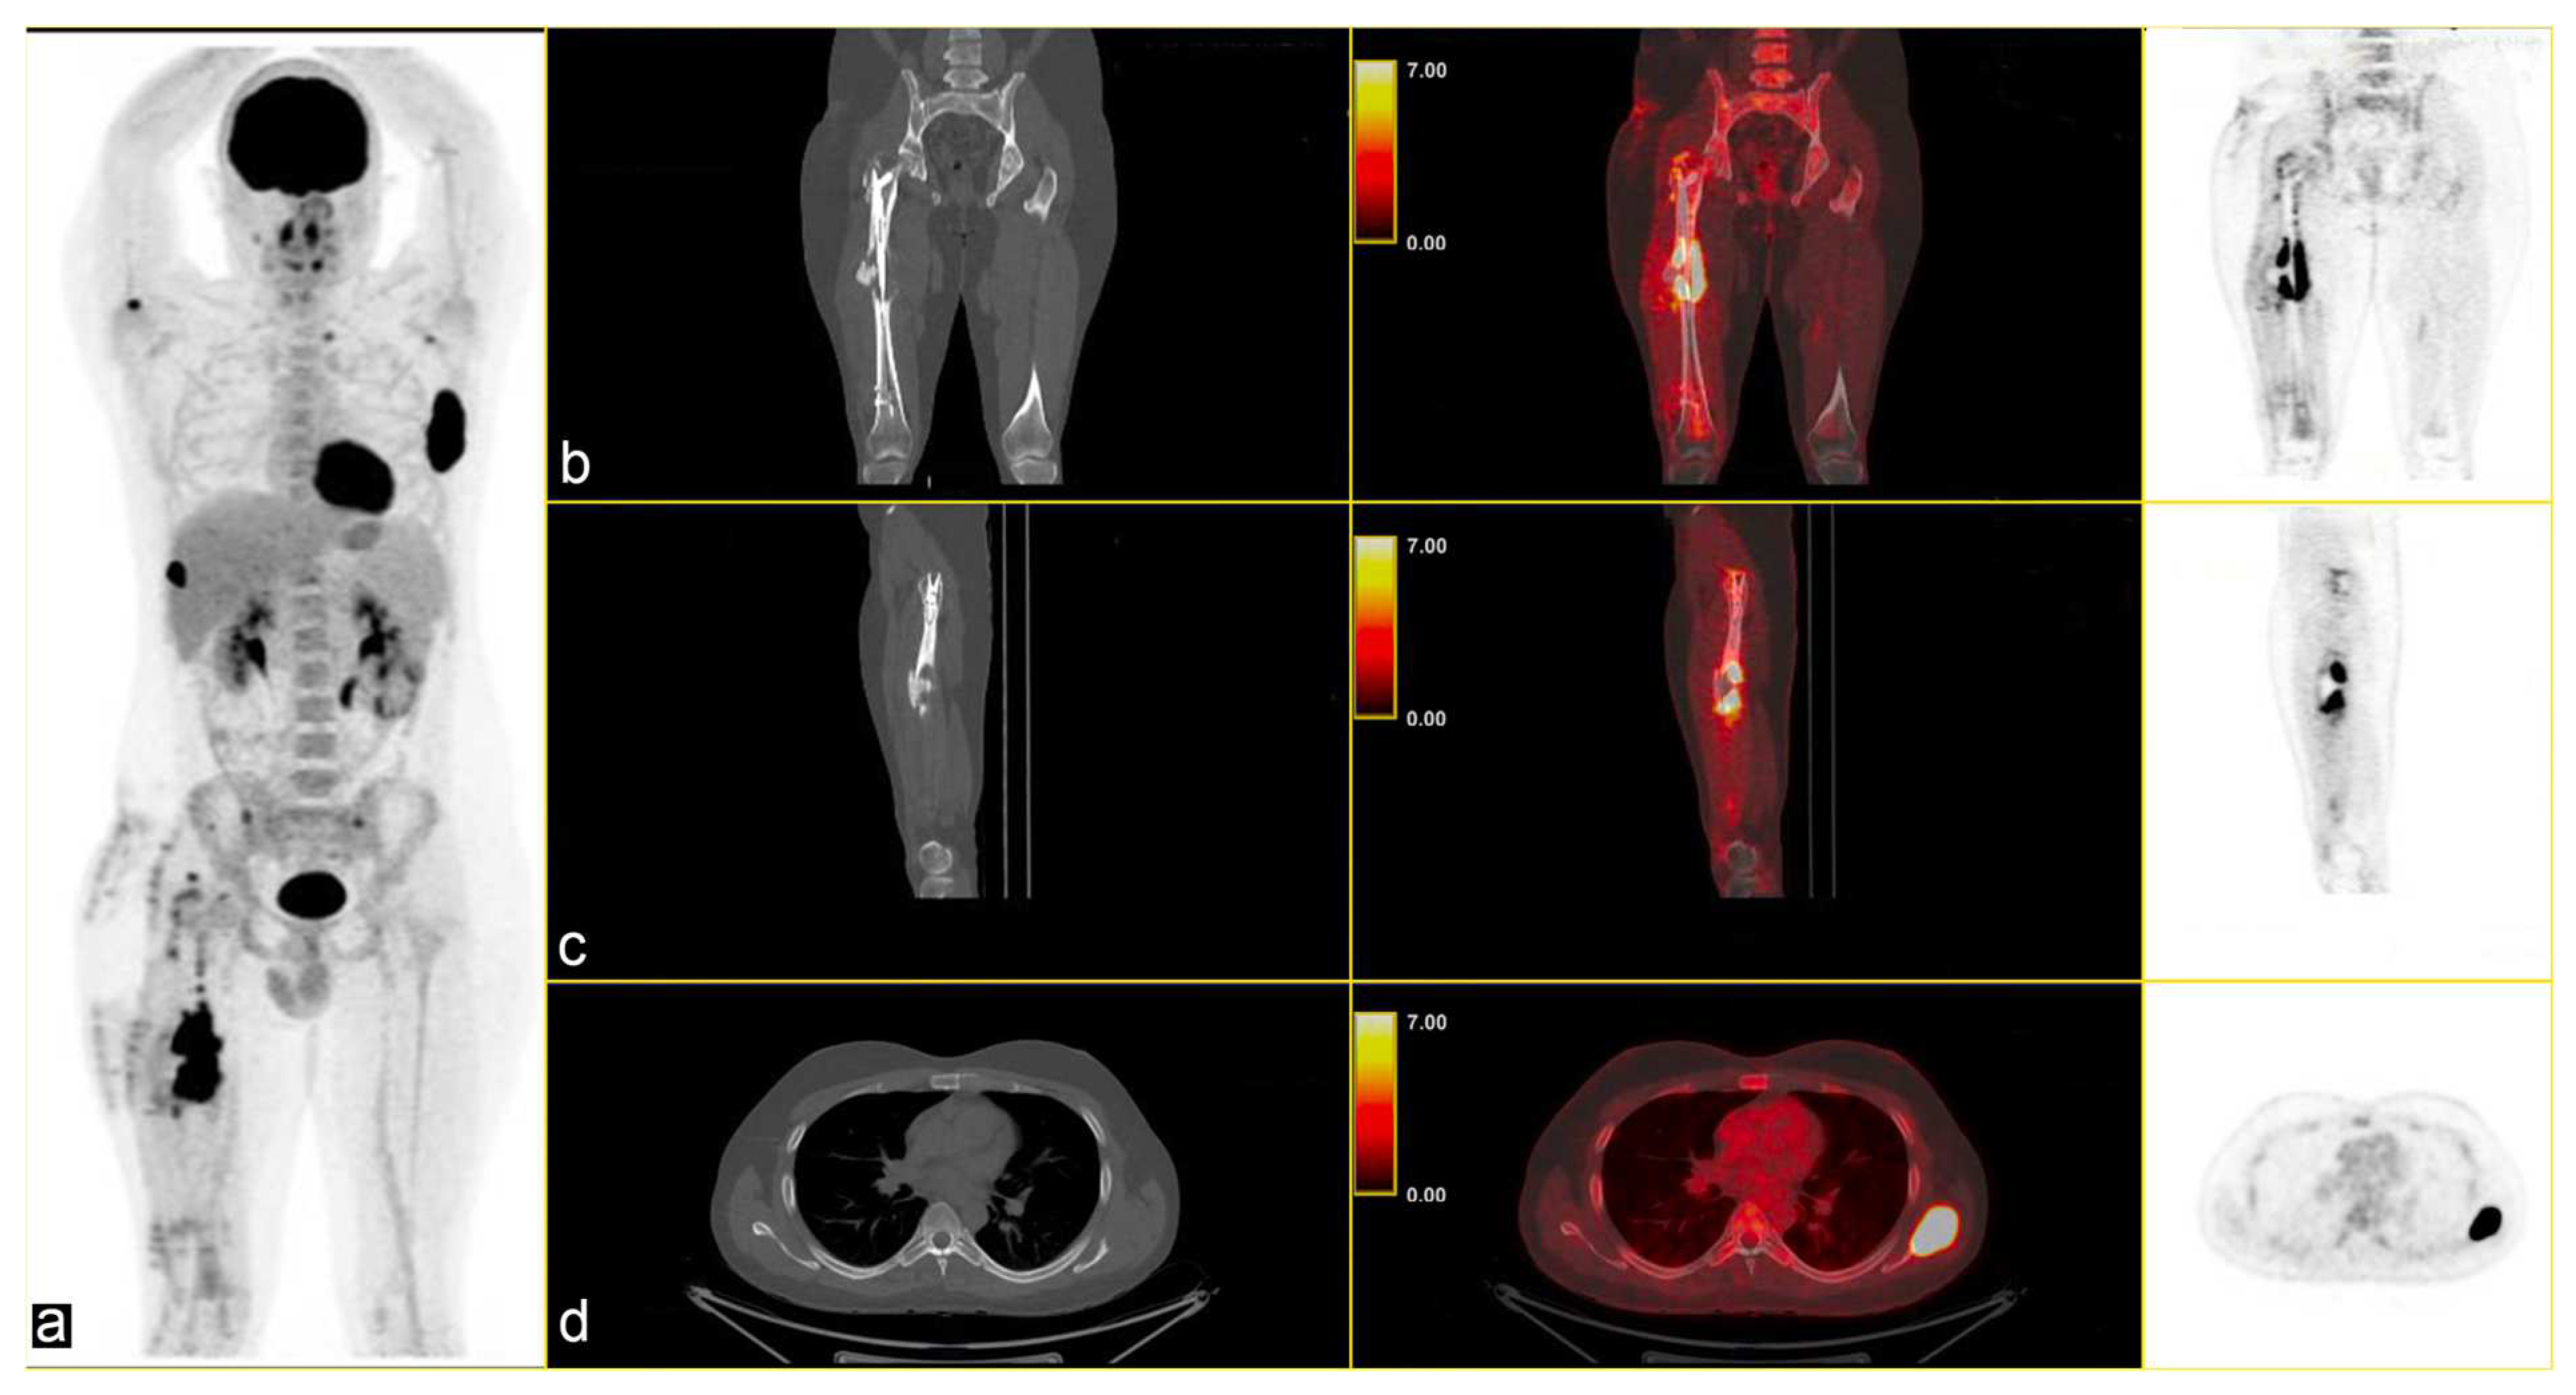

Following instrumental and clinical disease progression, the patient was treated with Sirolimus (an m-TOR inhibitor). At the first re-evaluation, instrumental progressive disease (PD) was observed with a moderate increase in bone SUVmax, particularly in the left scapula (SUVmax 34.8 vs. 31), and by the appearance of new lesions, such as the right iliac wing, numerous pulmonary nodules (SUV max 6) and lymph nodes in the left axilla (SUVmax 6.1) [Figure 3].

Figure 3.

PET/CT fused images show large hypermetabolic lesions in (a) the right femur, (b) the left scapula (with erosion of the cortical part), (c) thickened osteogenic lesions in the pelvis and bilateral iliac wings (thickened osteogenic lesions in with lower SUVmax: 6.7). From left to right CT PET/CT fused images and PET images.